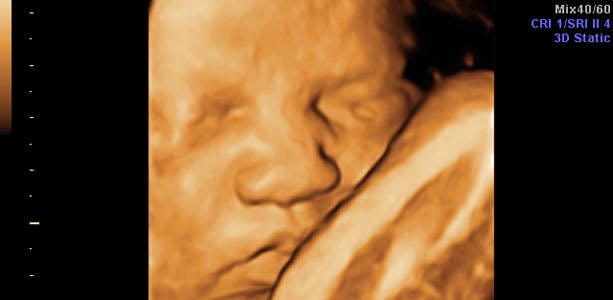

Gravid uge 36: Tæt på at være fuldbårent

Er nu tæt på at være fuldbårent, da den normale fødsel defineres som fødsel fra uge 37+0 til uge 42+0. Hvis du føder nu, vil barnet være smurt ind i pæne mængder fosterfedt, som aftager, desto tættere du føder på terminen. I slutningen af ugen måler barnet cirka 45 centimeter og vejer omkring 2750 gram. Lårbenet måler cirka 6,7 centimeter, maveomkredsen cirka 32,5 centimeter og hovedet cirka 8,9 centimeter i diameter.